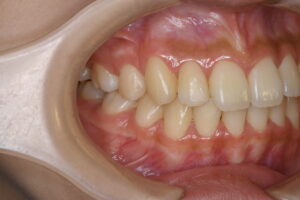

実際の症例紹介(20代女性/裏側ワイヤー矯正)

治療前

治療後

・主訴:八重歯と前歯の突出

・治療法:裏側からのワイヤー矯正(リンガル)

・治療期間:約1年半〜2年(目安)

・予想される副作用・リスク:装置装着後の違和感・疼痛、発音のしづらさ、一時的な咀嚼効率低下、ブラッシング不良によるむし歯・歯周病リスク など

※写真は代表的な症例です。口腔内の状態により治療法や期間は異なります。詳細は初診相談でご説明します。